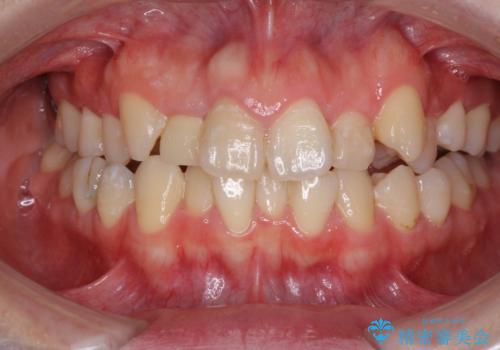

- 上下のデコボコと奥歯の咬みにくさを気にして来院された患者様です。

上顎骨の幅が下顎骨よりも小さいので、拡大装置により骨幅を広げて上下関係を改善し、その後インビザラインにて歯並びを整えることとしました。

上下の骨幅を改善したことで、スムーズに歯列矯正を行うことができました。

奥歯の咬み合わせを改善する必要があったため、治療は長期化しましたが、きっちりと仕上げることができました。